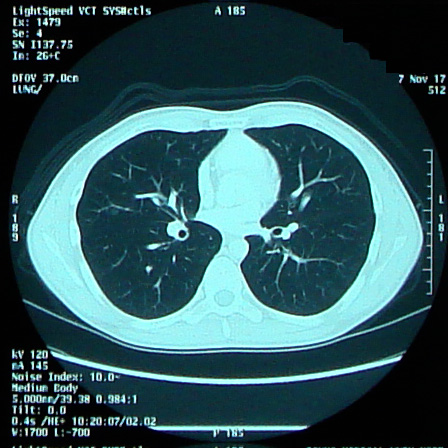

前回の「肺の影」のため間隔を詰めての検査。

9時半に病院到着。時間があるので先に採血へ。 30人待ちくらいか。今日は多いぞ。たまに機器トラブルもあるらしいが、なんだろう今日は。 その後予定通りCTを撮り帰宅。 29日の外来で結果を見る&聞く。

「結婚記念日でもある11/1にどうしても退院しておきたい」と強く思っていたあの日々からもう一年か。 無事に迎えられてよかった。 17日にCTの再検査が待っているのだが、とりあえず1年経過!

が、現実は仕事も忙しい時期であり、そう簡単には希望の生活にはならない。 今週で仕事の大きな山が一つ片付く。それ以降は、もう体に負担のかかる生活はしたくないものだ。 8月は70時間近い残業をしている。9月は52時間。 目標とする、希望する、残業時間は20時間以内である。 次回CTは11/17である。 この1ヶ月の生活で影には消えていただきたいと思う。 マーカー類はすべて正常で問題なし。 リンパ節も変化なし。 だが、肺に薄い影あるとこのとこ。本当に薄ーい。わかるかなぁ。。。 ちなみに、直ちに転移再発というわけでもなく、放射線科の意見では「違う」とのこと。 「違う」だろうけど念のため心配なので2ヵ月後に再検査ということにした。 午前中はやや心理的に混乱したな、、、 なにしろリンパの次は肺、その次は脳というのが転移の順番である。 そりゃ頭の中がぐちゃぐちゃになりますよ。 でもまぁ「違う」だろうとの判断が出てるし、マーカーも陰性だし。 最近忙しかったのがよろしくなかったかも。 体が「このままの生活じゃ危ないよ」と危険信号を出したのかな。 と嫁と話をしました。 実際問題、今自分ができることと言えば、結局生活習慣の改善くらいなので、それを実践します。